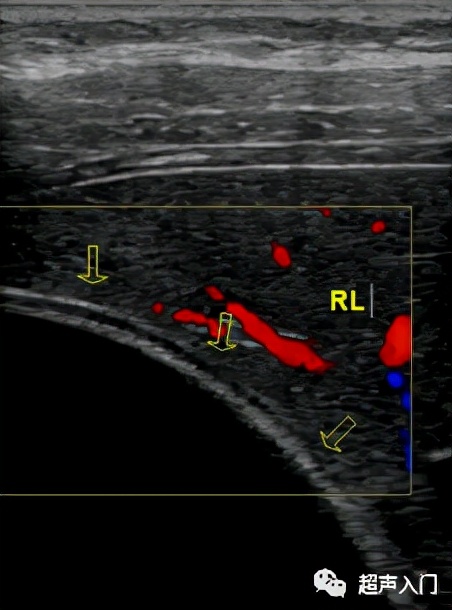

彩色多普勒:表现为无彩色血流信号,但在病灶并发感染则可在炎性区出现彩色血流。

图源:人卫出版社教材及课件